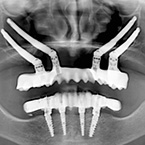

3. Radiografía tratamiento final. A los 6 meses de la cirugía.